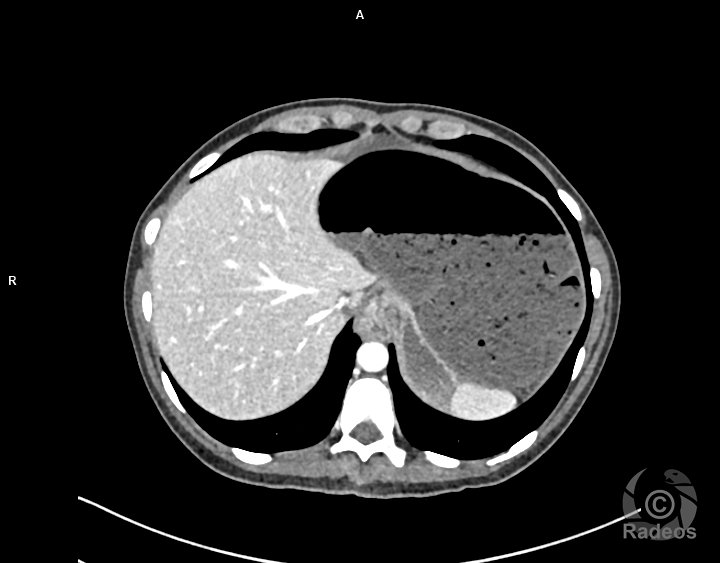

Aspect IRM d'une fibromatose profonde de la paroi abdominale. Découverte fortuite d'un angiome hépatique gauche.

Fibromatose profonde de type desmoïde